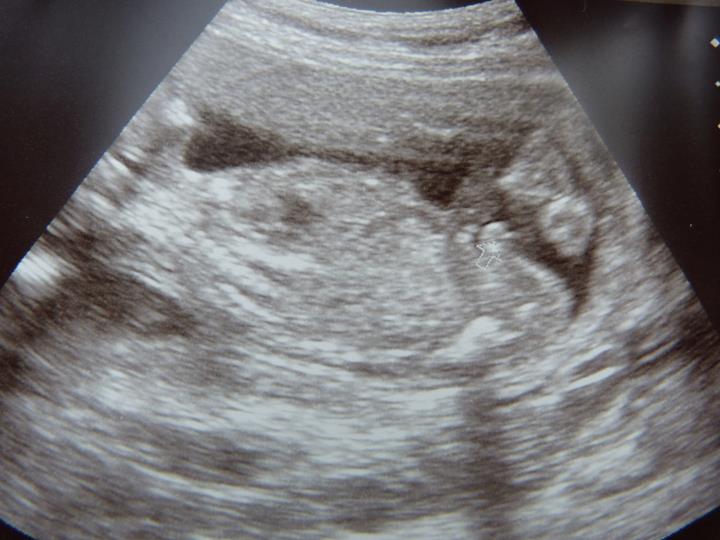

I am 99% certain that my tech was right and I'm having another boy, but just out of interest I wondered if anyone knew how accurate sideways profile ultrasound images are to tell gender at 19 weeks compared to potty shots?

I really wanted a potty shot but the tech didn't do one at all and stuck to sideways profiles for pretty much everything. It looks pretty obvious that there are boy bits there but of course as I was hoping for a girl part of me wonders whether it could be swollen girl bits. Is that less likely to be the case on a sideways profile?

Also I heard somewhere that the testicles don't descend until later than 20 weeks but on my scan pic it looks like you can see them sitting inbetween the legs as you can see from the 'money' shot she gave us here:

I think I am just grasping at straws because my other two boys were so much clearer on the ultrasound. This time I thought it was a boy earlier on in the scan but wasn't sure if I had just seen the cord. Everyone I have shown this to so far as said definitely a boy so I know it most probably is, and I'm actually coming round to that idea but I just wondered why the tech only did a profile shot and not a potty shot which would surely have shown everything very clearly? xx